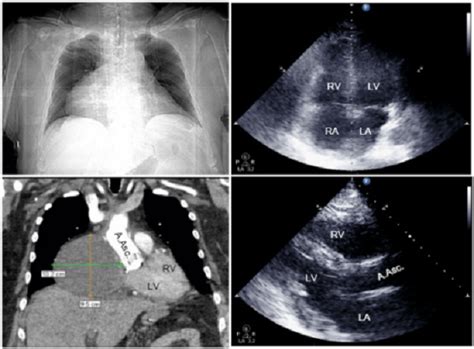

Untuk mendiagnosis tamponade jantung, dokter akan melakukan pemeriksaan fisik dan tes diagnostik seperti CT scan atau MRI. Jika ditemukan tanda-tanda tamponade jantung, dokter akan merujuk pasien untuk menjalani perawatan lebih lanjut.